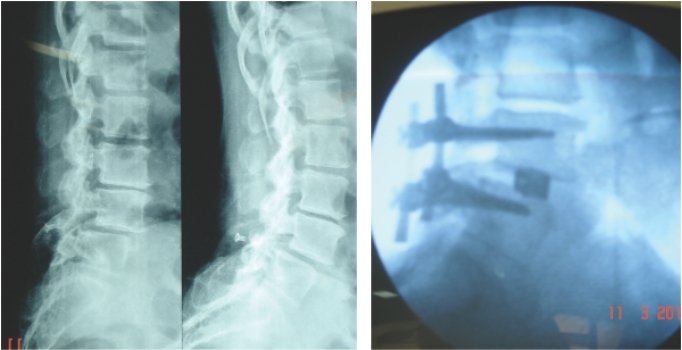

old age patient with osteoporotic spine minor- major trauma---collapse of vertebra

if not healed,vertebroplasty done through only a small hole in the skin, under image

guidance, patient made to stand and walk directly from the operation theatre